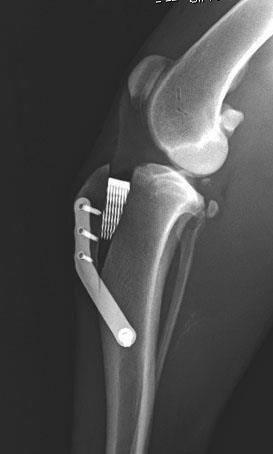

TPLO - Tibial Plateau Leveling Osteotomy

La tecnica TPLO (Osteotomia di livellamento del piatto tibiale) è attualmente una delle metodiche chirurgiche più utilizzate per il trattamento della rottura del legamento crociato craniale nel cane. Essa revede l’esecuzione di un'osteotomia radiale, eseguita con strumentario apposito, la rotazione caudale del segmento prossimale tibiale e la stabilizzazione dei monconi tibiali mediante placca.

Questa tecnica non prevede alcuna sostituzione del legamento crociato in quanto, mediante una modificazione della geometria articolare, permette di ottenere l'annullamento di forze indesiderate. In particolare, mediante la correzione dell’inclinazione del piatto tibiale, si propone di assicurare la stabilità dinamica cranio-caudale a carico dell’articolazione del ginocchio durante la fase d’appoggio del passo.

I vantaggi di questa tecnica chirurgica comprendono la precisione geometrica e il mantenimento nella posizione dell'articolazione del ginocchio, senza modificarne la biomeccanica.